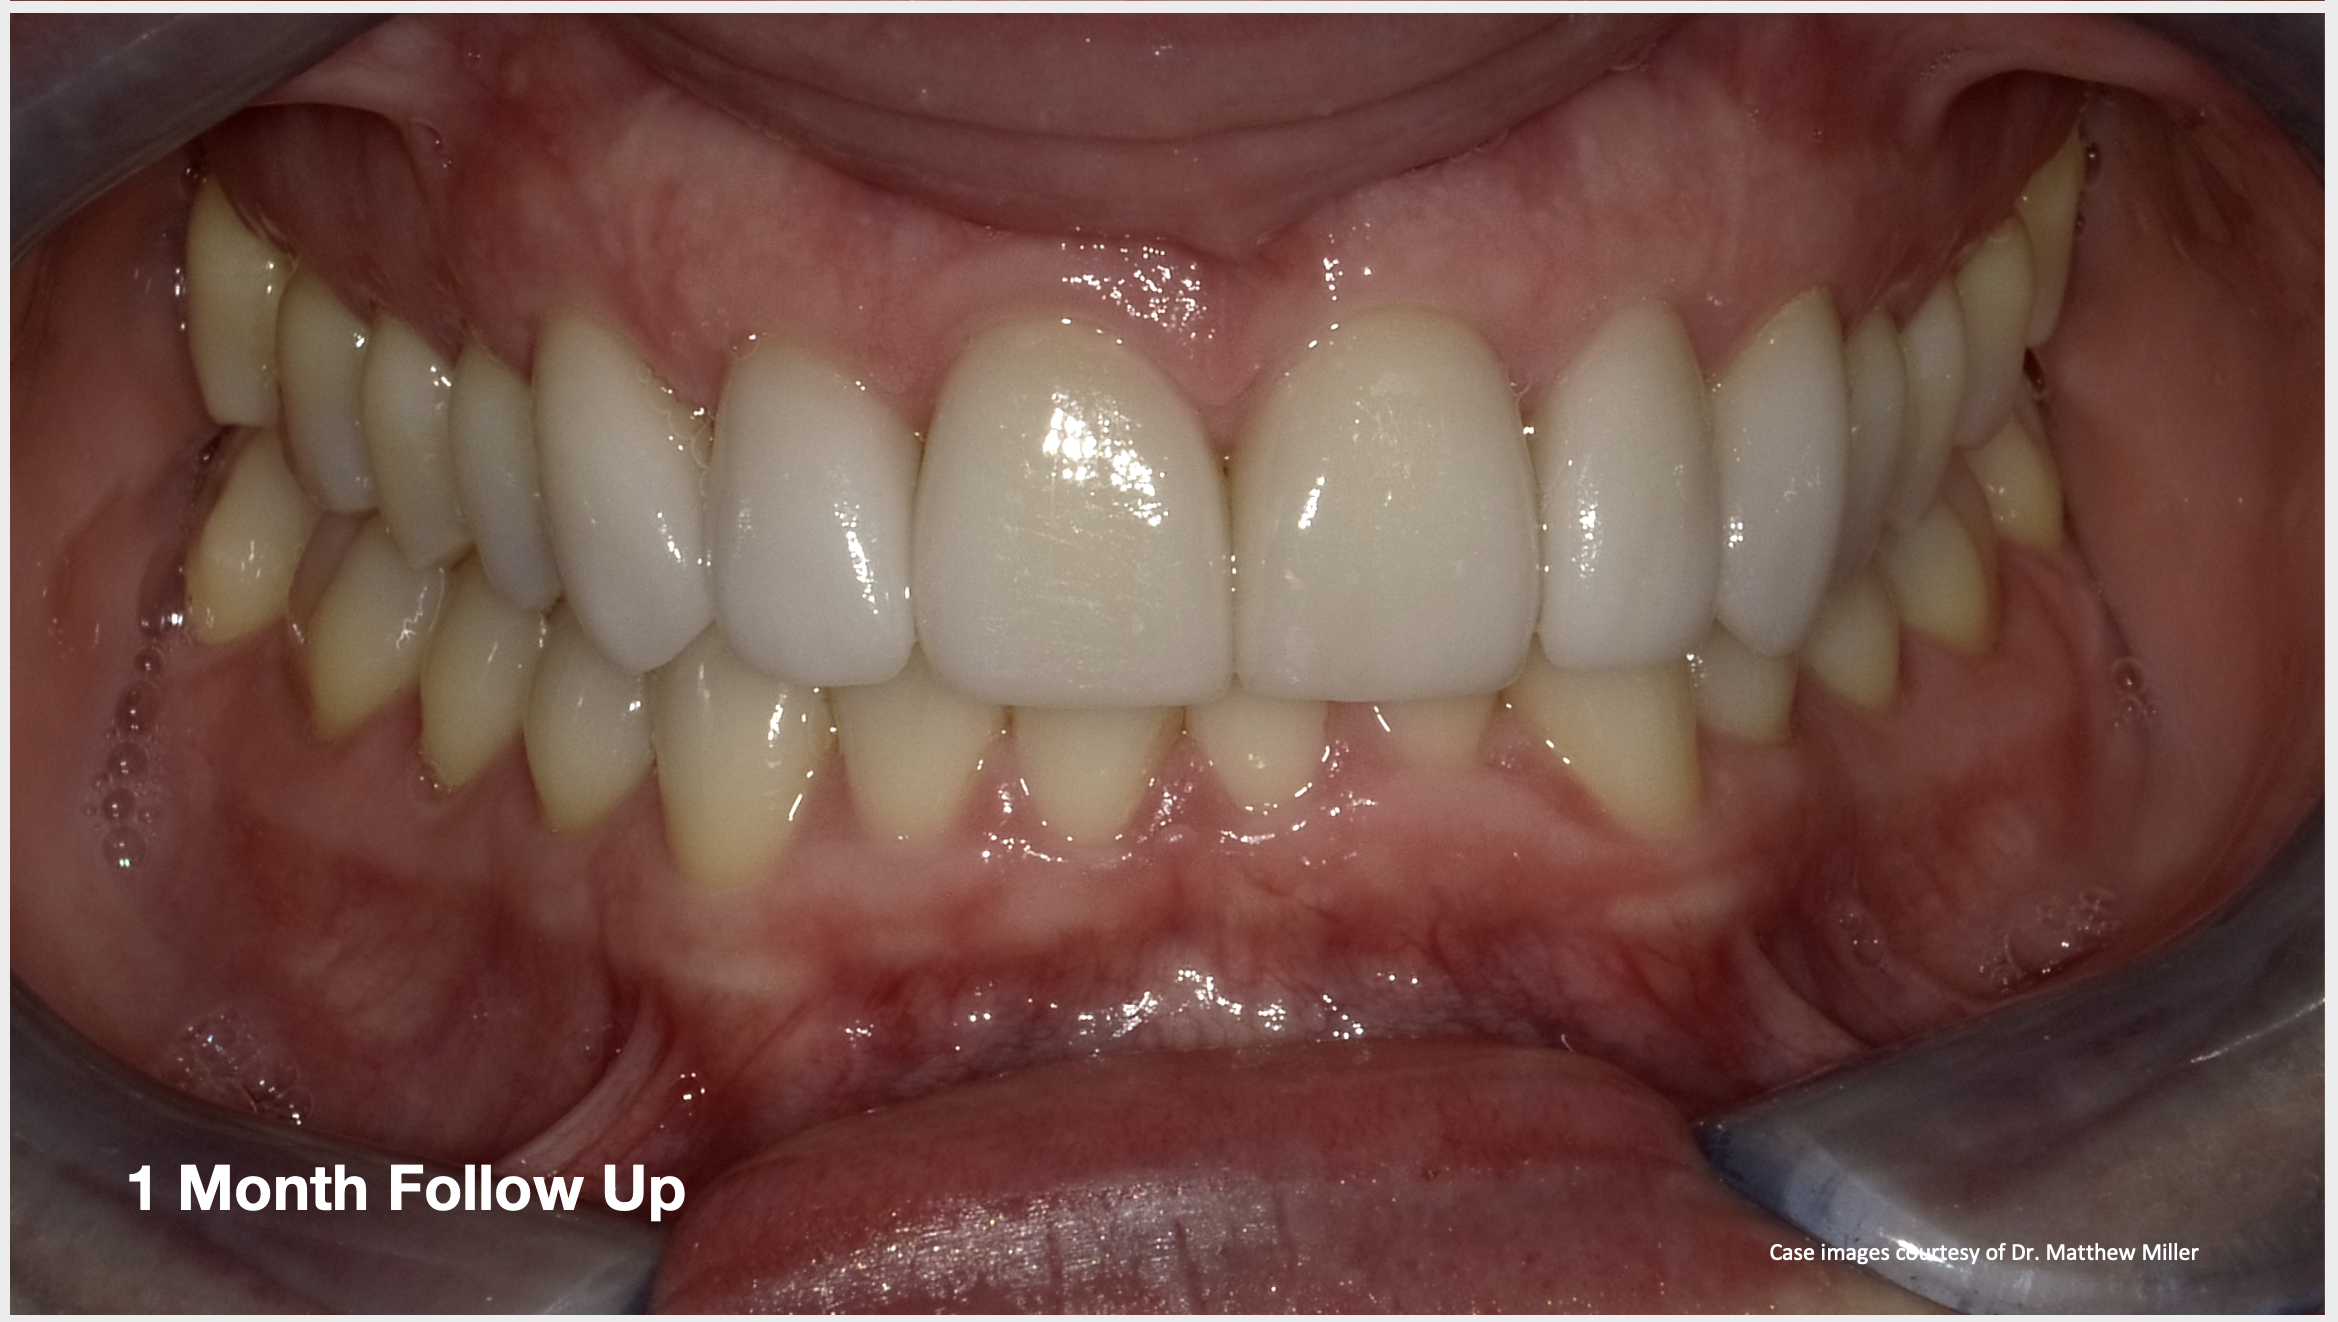

In another case, the patient presented with very thick, bulky, over-contoured veneers done on teeth Nos. 7 through 10 when she was a teenager. There also was some recession and staining at the margins (Figure 12). The clinician decided to restore teeth Nos. 6 through 11. A preparation design was required with provisionals removed. As tooth structure could not be regrown, the practitioner made the best of the situation. There was good gum health, which is important for isolation and marginal seal. The clinician cemented with a universal, doing six units at one time. Minimal cleanup was required. At a 1-month follow-up visit, although tissue still was settling in, the contours were natural. After a year (Figure 13), the gum filled in nicely and was in excellent health, and there was good color stability and seamless marginal integrity.